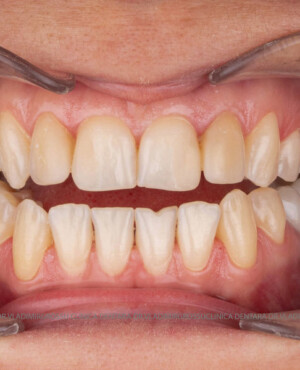

Cazuri clinice

Caz 1

Caz 2

Transformările estetice și impactul reabilitării asupra vieții pacienților

Reabilitarea dentară produce o schimbare vizibilă și profundă în aspectul pacientului, cu efecte pozitive evidente asupra stimei de sine și a calității vieții. Mulți pacienți relatează bucuria redobândirii funcției masticatorii și dispariția complexelor legate de aspectul dentar.